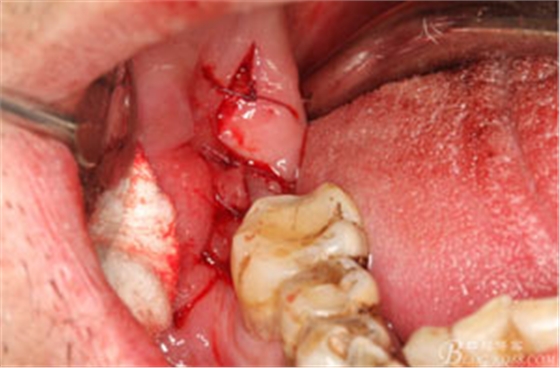

圖6.行角形瓣切開、翻瓣、暴露骨面,可見48牙冠表面有炎性肉芽組織